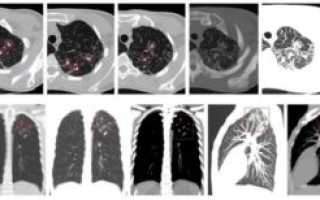

В числе наиболее эффективных способов определения туберкулезного заболевания на ранних стадиях его развития является компьютерная томография. Первичный туберкулез на КТ легких отображается в виде разрастаний на корнях органов дыхания. Еще врач может заметить следы патологических изменений тканей.

При выполнении тестов делают снимки с разных ракурсов и проекций. Потом специалист изучает результаты и составляет подробное описание.